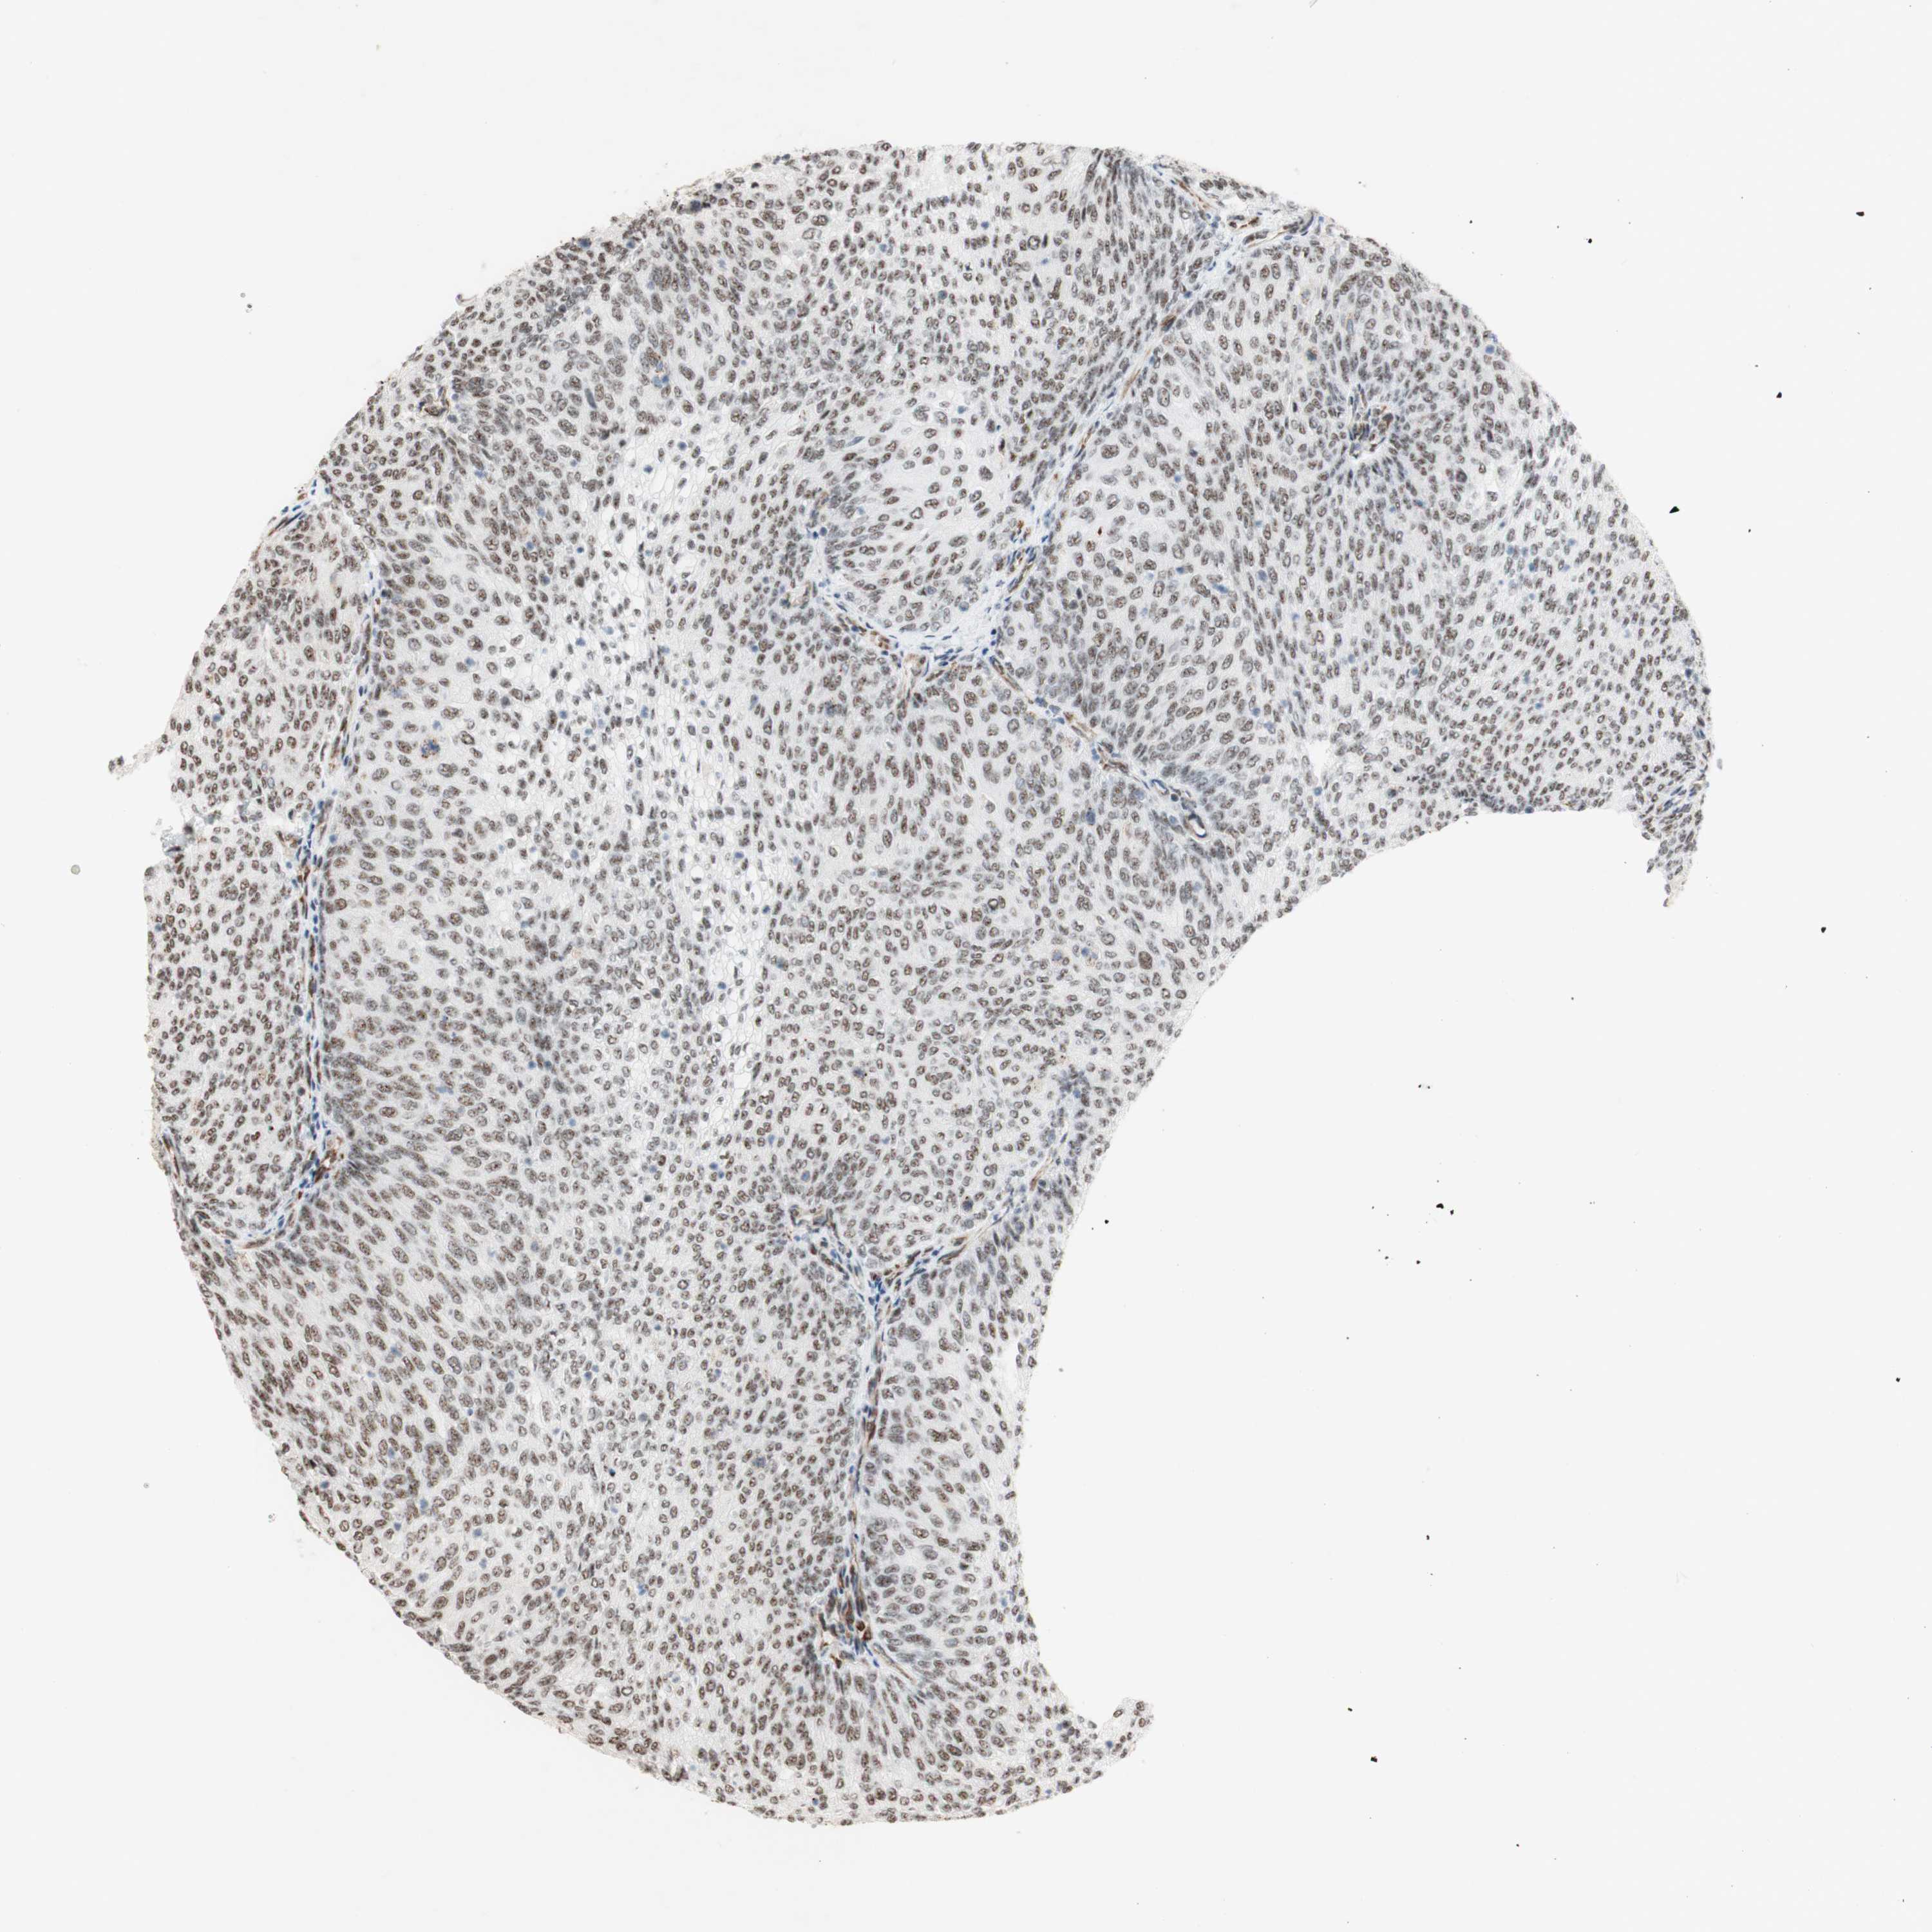

UROTHELIAL CANCER - Protein expressioni

A mouse-over function shows sample information and annotation data. Click on an image to view it in a full screen mode. Samples can be filtered based on level of antibody staining by selecting one or several of the following categories: high, medium, low and not detected. The assay and annotation is described here.

Note that samples used for immunohistochemistry by the Human Protein Atlas do not correspond to samples in the TCGA dataset.

Antibody stainingi

Antibody staining in the annotated cell types in the current human tissue is reported as not detected, low, medium, or high, based on conventional immunohistochemistry profiling in selected tissues. This score is based on the combination of the staining intensity and fraction of stained cells.

Each image is clickable and will lead to virtual microscopy that enables deeper exploration of all samples and also displays staining intensity scores, fraction scores and subcellular localization as well as patient and tissue information for each sample.

Antibody HPA011352

Antibody CAB012273

Staining

High

Medium

Low

Not detected

Intensity

Strong

Moderate

Weak

Negative

Quantity

>75%

75%-25%

<25%

None

Location

Nuclear

Cytoplasmic/membranous

Cytoplasmic/membranous,nuclear

Urothelial carcinoma, Low grade

Urothelial carcinoma, High grade